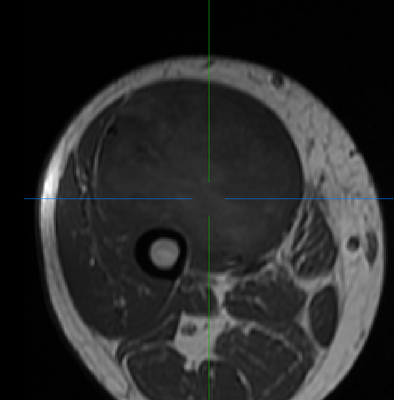

(Left/Top) T1 registered image without bias correction. (Right/Bottom) T1 image post bias correction and registration. Higher contrast and greater uniformity is apparent.